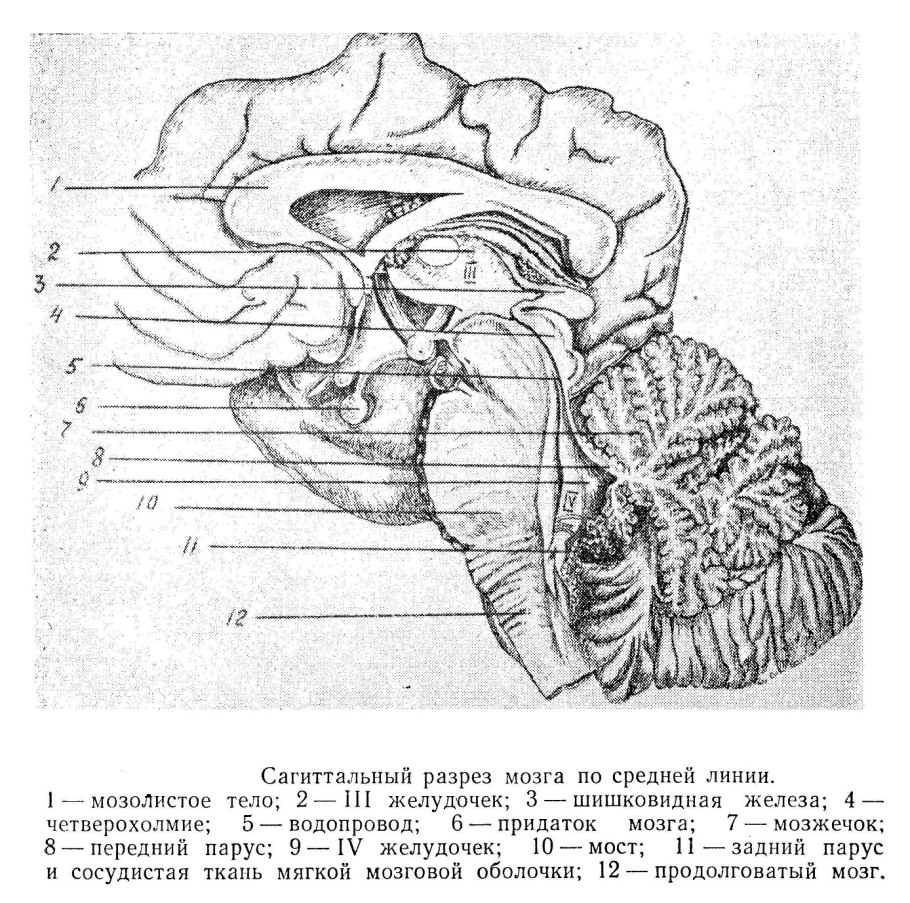

Каллозотомия мозолистого тела

Комиссуральные волокна головного мозга

Мозолистое тело человека